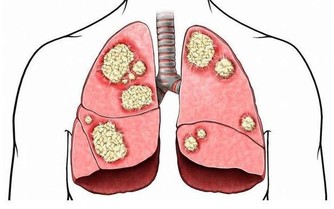

睡眠是人恢復精神和體力的重要途徑,夜間睡眠質量直接影響情緒和身體健康。近日,美國《神經病學》雜誌上刊載了北京大學公共衛生學院李立明教授團隊的新研究,根據在中國進行的一項針對50萬人、隨訪長達10年的大規模研究發現,失眠不僅折磨人的身心,還是心血管疾病的獨立危險因素。

此次研究分析顯示,平均隨訪9.6年期間,每周至少3天出現早醒、入睡困難或睡眠維持困難、白天困倦等失眠症狀的中國成年人,發生心血管病的風險分別為7%、9 %、13%。失眠症狀越多,心腦血管疾病發生風險越高。與沒有失眠症狀的人相比,有1個、2個或3個失眠症狀的人,發生心血管病的風險分別增加7%、10%、18%。而且,有失眠症狀的人發生心肌梗死、中風(腦卒中)或其他心腦血管疾病的風險明顯增加。儘管失眠在老年人群中發生率更高,但研究發現,年輕人失眠與心血管病發生風險之間的關聯更密切。另外,失眠對之前沒有高血壓的人來說,害處也很大。

失眠已成為現代人生活中的常見問題,有些人是主動失眠,有些則是被動失眠。無論是主動還是被動,長期睡眠不好或熬夜的人,生物節律都會被打亂。睡眠不足會進一步導致交感神經興奮,人體內的兒茶酚胺類物質分泌增高,促進炎症反應,導致高血壓、冠心病、心力衰竭及心律失常等心血管疾病的發生與發展,並增加相關心血管事件的發生率。因此,失眠患者應儘早予以臨床干預,以減少其對機體的損害及各種心血管事件的發生。

失眠不僅會導致心血管疾病,對已有心血管疾病的患者,更會令病情反復發作,乃至加重,長此以往,持續高血壓還會傷害心臟與大腦,加重左心室的負擔,導致心肌肥厚,出現心臟擴大、呼吸困難等心功能不全症狀。可見,不管是健康人群還是心血管疾病患者,都需要保證充足優質的睡眠。